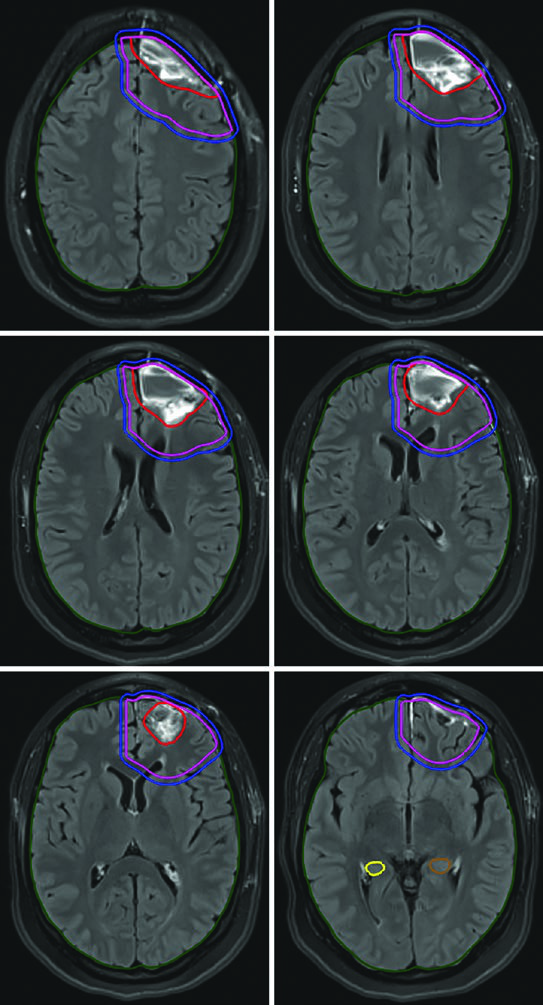

O ponto central é este: a delineação precisa tanto dos volumes-alvo quanto dos órgãos de risco determina qual técnica será mais vantajosa para cada paciente. E para isso, a corregistração de RM diagnóstica no CT de planejamento não é opcional — é fortemente recomendada. As sequências T1 pós-contraste e FLAIR permitem visualizar tanto o tumor residual quanto o edema perilesional, enquanto sequências T1 simples e 3D-T2/CISS ajudam a delinear estruturas como hipocampo e nervos cranianos. Para mais contexto sobre os princípios gerais de delineamento, confira nosso guia completo sobre delineamento de volume alvo na radioterapia.

A dose padrão para gliomas de alto grau é de 59,4–60 Gy com fracionamento convencional. Para pacientes idosos, frágeis ou com performance status limitado, esquemas hipofracionados são uma alternativa validada: 40,05 Gy em 15 frações ou até 25 Gy em 5 frações, com margens reduzidas (0,5–1 cm). A tabela a seguir resume os volumes recomendados por tipo tumoral.

| Glioma anaplásico (captante) | Cone-down sequencial: PTV1 50,4 Gy (1,8 Gy/fx), PTV2 59,4 Gy (1,8 Gy/fx); ou SIB: PTV1 54,45 Gy (1,65 Gy/fx), PTV2 59,4 Gy (1,8 Gy/fx) | GTV1: volume T2/FLAIR; GTV2: cavidade pós-operatória + tumor residual na T1 pós-contraste | CTV1: 1,5 cm restrito anatomicamente; CTV2: 1,0 cm restrito | 0,3–0,5 cm |

| Glioma anaplásico (não captante) / Astrocitoma difuso IDH-wild type | PTV1: 59,4 Gy (1,8 Gy/fx) | GTV: cavidade pós-operatória + tumor residual em T2/FLAIR | CTV: 1,5 cm restrito anatomicamente | 0,3–0,5 cm |

| Glioblastoma | Cone-down: PTV1 46 Gy (2 Gy/fx), PTV2 60 Gy (2 Gy/fx); ou SIB: PTV1 50–51 Gy (1,67–1,7 Gy/fx), PTV2 60 Gy (2 Gy/fx) | GTV1: volume T2/FLAIR; GTV2: cavidade + tumor residual na T1 pós-contraste | CTV1: 2 cm restrito anatomicamente; CTV2: 2 cm restrito | 0,3–0,5 cm |

Um ponto prático fundamental: as expansões anatomicamente restritas significam que o CTV não cruza a linha média, não invade a cisterna pré-pontina, não se estende pelo crânio e não ultrapassa o tentório para a fossa posterior. No entanto, tratos em risco para disseminação tumoral contralateral — como o joelho do corpo caloso — devem ser incluídos. Essa nuance aparece claramente nos casos de glioblastoma frontal em que o tumor se aproxima do corpo caloso.

Alguns erros recorrentes no planejamento de tumores malignos do SNC merecem destaque. O mais comum é aplicar expansões isotrópicas sem respeitar as barreiras anatômicas. O CTV de um glioblastoma frontal não deve cruzar a linha média — a menos que o joelho do corpo caloso esteja em risco, caso em que essa estrutura deve ser explicitamente incluída. Outro erro é ignorar a diferença entre as sequências de RM: o GTV1 deve ser baseado no FLAIR (edema perilesional), enquanto o GTV2 usa a T1 pós-contraste (doença captante residual).